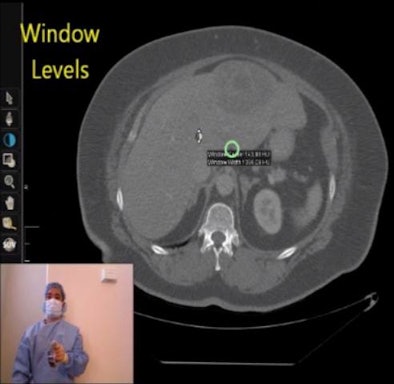

![]() |

| Screenshot shows the Hillcrest Labs Loop Pointer for intraoperative imaging review. Users can direct the mouse cursor (blue circle cursor) by moving the gyroscopic-based mouse in space. In this case, Tan is using the window/level function to enhance visualization of the liver lesion. The toolbar is at the left of the display. |